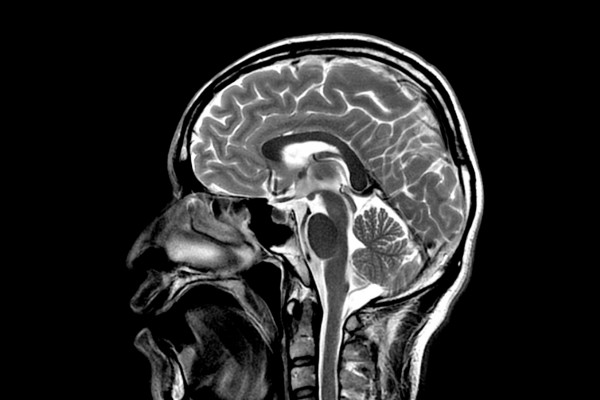

В ходе игры специалистам, проводившим функциональную магнитно-резонансную томографию мозга участников, удалось предсказать выбор испытуемых в 71,8% случаев.

Причем, участки мозга, по которым можно предсказать, рискнет человек или нет, как правило, находились в областях мозга, отвечающих за контроль поведения, рабочую память и внимание. Как отмечают исследователи, риск в какой-то степени может оказаться результатом ошибки контролирующих систем, которые требуются для выбора безопасного решения.

Кроме того, ученые подчеркивают, что для предсказания выбора игроков было достаточно грубых данных. Они показывали усредненную активность отделов мозга, связанных с рисковым поведением, а также областей, которые отвечают за избегание риска.